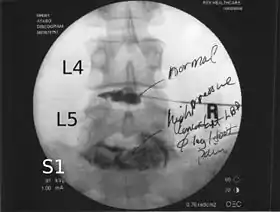

![]() Lumbar provocative discography showing a degenerated disc, L5-S1 with normal disc L4-L5 | |

Spinal MRI is the imaging of choice to investigate the spine and intervertebral discs.[1] Meanwhile, lumbar discography is used to demonstrate degeneration and herniation of lumbar intervertebral discs by injecting a dye into the nucleus pulposus of the discs. The procedure is also used to reproduce pain back pain for those who have such symptoms. Lumbar discography is also used to access the response of a subject to anaesthetic injection. Other uses include suspected discogenic pain without radicular sign (pain travelling to lower limbs along a dermatome) and confirmation of normal intervertebral discs above and below a site before spinal fusion.[1] However, evidence supporting the usefulness of lumbar discography in recognizing intervertebral disc problems is limited.[1] There is no role for cervical or thoracic discography in diagnosing disc pathologies at the cervical or thoracic regions.[1][2]

Non-ionic contrast media such as iopamidol and iohexol are used.[1] Needles are inserted through the back into the disc near the suspect area, guided by fluoroscopic imaging. Fluid is then injected to pressurize the disc, and any pain responses are recorded.